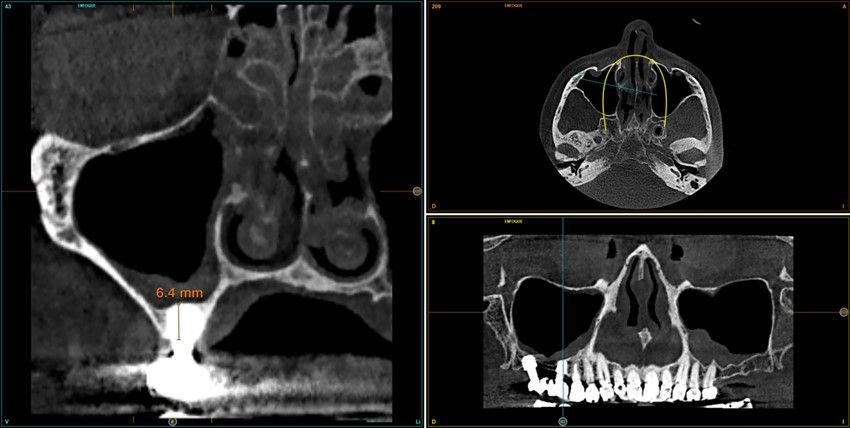

Resultados. Fueron reclutados 13 pacientes en los que se insertaron 30 implantes. Una vez insertados y cargados los implantes, la altura media final fue de 9,68 mm (+/- 2,66), lo que supone una ganancia promedio de 5 mm. A los 10 años, se observó una disminución media de la altura ósea ganada en los implantes en conjunto de 0, 29 mm (+/- 0,77). La media de la pérdida ósea mesial fue de 0,73 mm (+/- 0,75 mm) y la media de la pérdida ósea distal fue de 0,98 mm (+/- 1,2 mm). La supervivencia fue del 100%.

Results.Thirteen patients were recruited and 30 implants were inserted. Once the implants were inserted and loaded, the mean final height was 9.68 mm (+/- 2.66), which represents an average gain of 5 mm. At 10 years, there was a mean decrease in the overall bone height gain of the implants of 0.29 mm (+/- 0.77). The mean mesial bone loss was 0.73 mm (+/- 0.75 mm) and the mean distal bone loss was 0.98 mm (+/- 1.2 mm). Survival was 100%.

Nuestro grupo de estudio modifica esta técnica de elevación transcrestal utilizando para el acceso unas fresas de corte frontal que permiten eliminar la cortical inferior del seno con lentitud sin dañar la membrana de Schneider, eliminándose los osteotomos y el malestar que genera su accionamiento mediante el martillo6-7. Inicialmente el procedimiento fue concebido para ser empleado con material de injerto al igual que el abordaje convencional, pero posteriormente se presentaron variaciones del procedimiento donde se insertaban los implantes sin injerto, utilizándose el propio implante como mantenedor de espacio entre la membrana de Schneider y la cavidad creada entre la membrana y la cresta, permitiendo que esta cavidad no se colapsase y posteriormente fuera colonizada por nuevo hueso7-11.

Los senos tratados con la técnica de elevación transcrestal sin material de relleno muestran un incremento de entre 2,5 mm12,13 hasta 4.4 mm14,15 en la altura ósea lograda sobre el ápice y una supervivencia de los implantes que se sitúa entre un 94 y un 100%16-17. En este trabajo se presenta un estudio retrospectivo donde se ha evaluado la inserción de implantes extracortos (5,5 y 6,5 mm) en zonas posteriores maxilares mediante la técnica de elevación de seno transcrestal con la fresa de ataque frontal sin la utilización de material de injerto, con un tiempo de seguimiento de 10 años para poder objetivar el comportamiento de los implantes a largo plazo y de la técnica empleada.